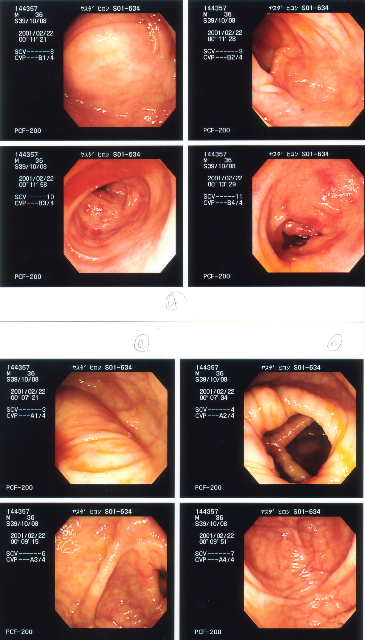

2001/2/22 大腸カメラ   下血も止まり、CRP値の0.0の時期。直腸、S状結腸の炎症はほとんど治まっているが、下行結腸、横行結腸に炎症が残っている(らしい)。食事は、この炎症がおさまってからとの事。